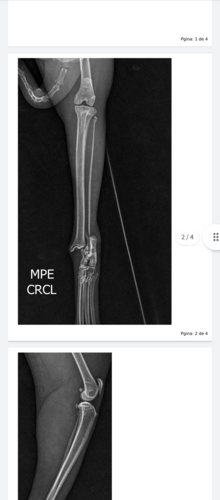

Meus amigos sei que as vezes não temos como ajudar o próximo mais venho pedir ajuda minha gatinha foi machucada por alguém que não tem amor ao próximo ela está o uma das patas traseira quebrada e eu não tenho condições para custear a cirurgia dela no momento se você puder me ajudar eu ficarei grato ou se puder compartilhar com alguém que ajude também ficarei grato por ajuda nessa corrente eu agradeço muito pela atenção de cada um de vocês obrigado e Deus abençoe sua vida…